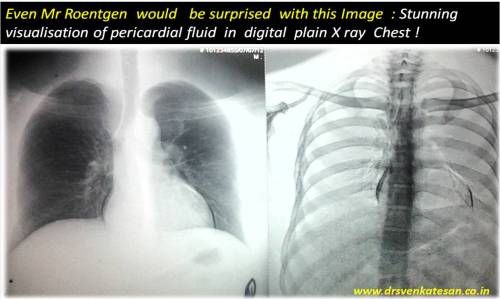

How did the pericardial fluid became radio opaque ?

This X-Ray surprised me . . . may be . . . Mr Roentgen as well !

Posted in cardiac radiology, Cardiology - Clinical, tagged pericardial effusion by xray chest, radi-opaque pericardial effusion on January 31, 2013| 1 Comment »